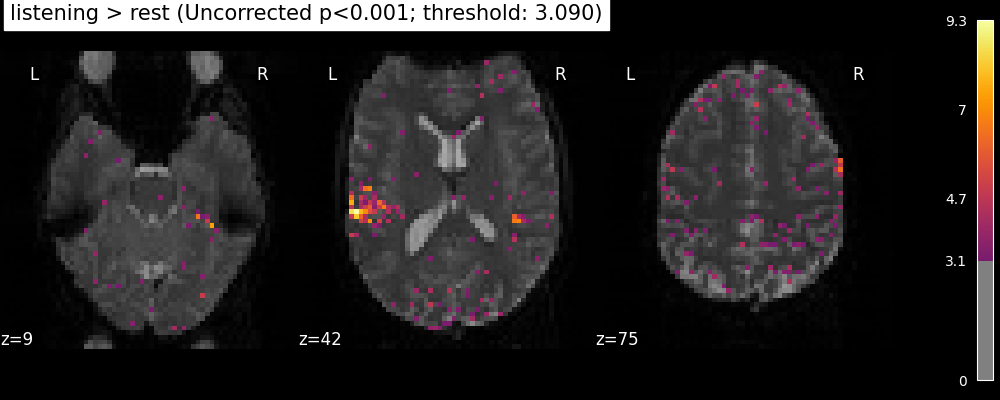

One should worry about the statistical validity of the procedure: here we used an arbitrary threshold of 3.0 but the threshold should provide some guarantees on the risk of false detections (aka type-1 errors in statistics). One suggestion is to control the false positive rate (fpr, denoted by alpha) at a certain level, e.g. 0.001: this means that there is 0.1% chance of declaring an inactive voxel, active.

from nilearn.glm import threshold_stats_img

clean_map, threshold = threshold_stats_img(

z_map,

alpha=0.001,

height_control="fpr",

two_sided=False, # using a one-sided test

)

# Let's use a sequential colormap as we will only display positive values.

plotting_config["cmap"] = "inferno"

plot_stat_map(

clean_map,

threshold=threshold,

title=(

f"listening > rest (Uncorrected p<0.001; threshold: {threshold:.3f})"

),

figure=plt.figure(figsize=(10, 4)),

**plotting_config,

show()

The problem is that with this you expect 0.001 * n_voxels to show up while they’re not active — tens to hundreds of voxels. A more conservative solution is to control the family wise error rate, i.e. the probability of making only one false detection, say at 5%. For that we use the so-called Bonferroni correction.